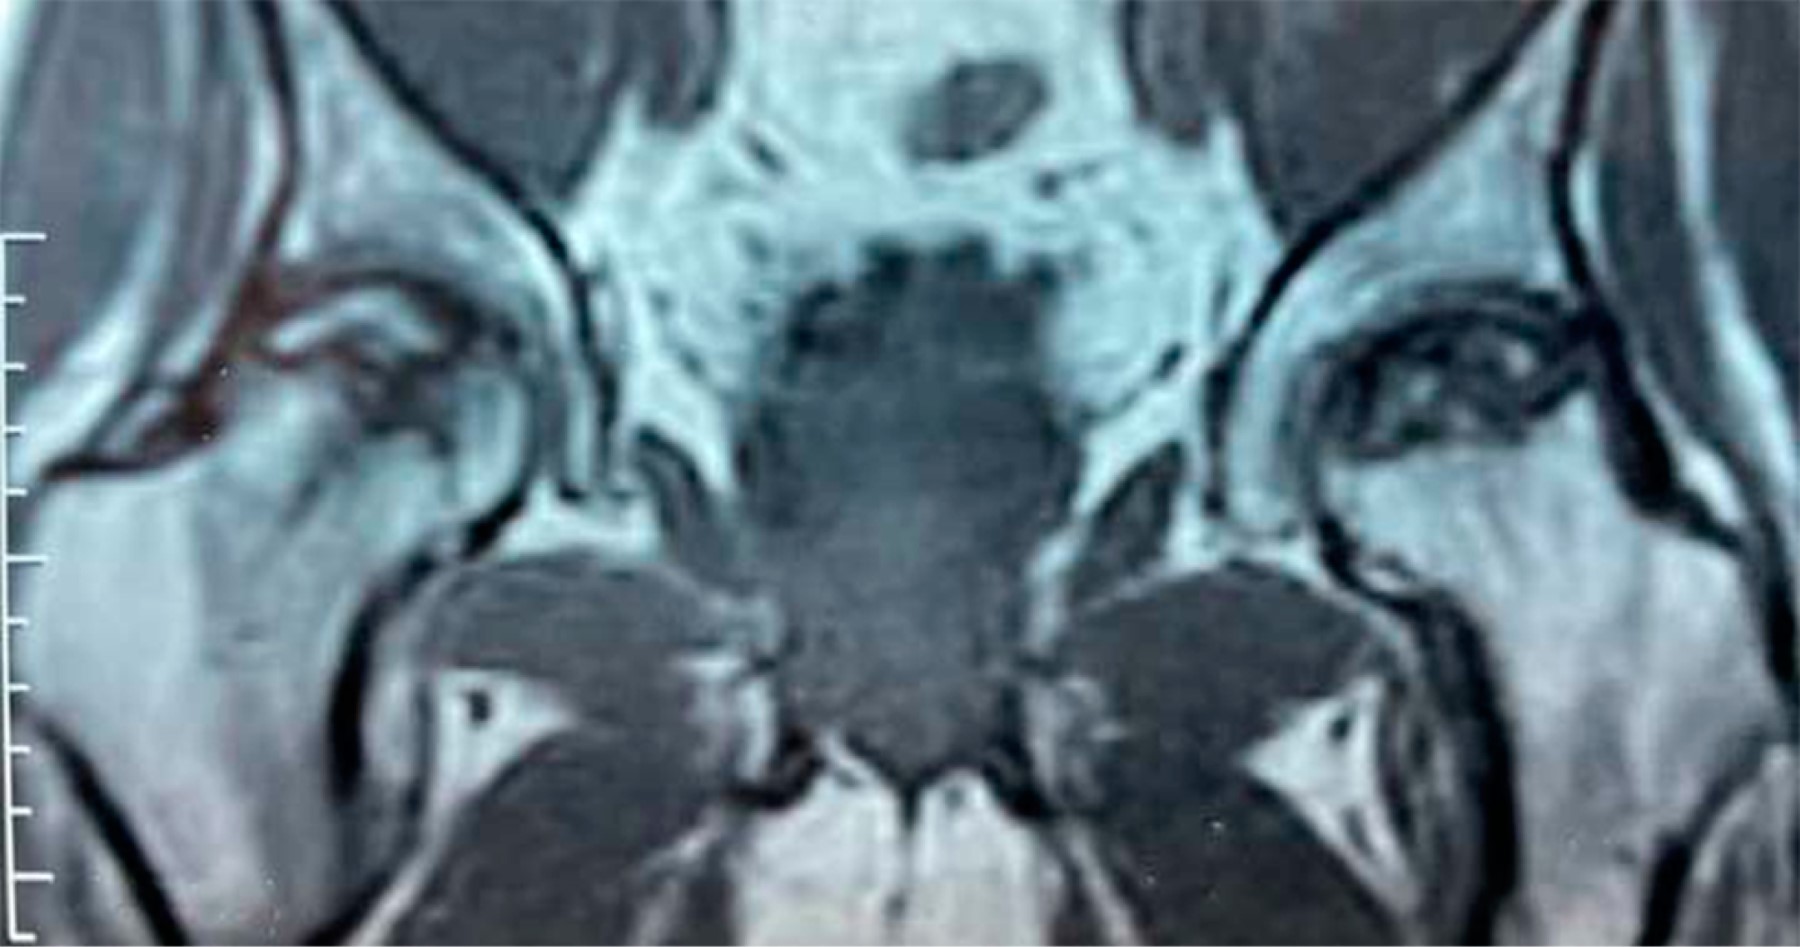

Todos los pacientes habían recibido corticosteroides como parte de su régimen de tratamiento para COVID-19 con dosis promedio de 480 mg, en un rango de 400 a 1,200 mg de hidrocortisona (o su equivalente –se adjunta tabla de conversión–) (Tabla 1). Estos pacientes mostraron síntomas clásicos de NAVCF caracterizados por un rápido deterioro funcional con sintomatología clínica de dolor, limitación a la carga y movilización. Asimismo, presentaron los cambios correspondientes en las imágenes de radiografías y resonancia magnética nuclear (RMN); los estadios de necrosis fueron clasificados según Ficat8 (Figuras 1 y 2). Se incluyeron estadios I a III de la clasificación dada la juventud de la serie y que no tenían artrosis con disminución del espacio articular.

Con base en la evaluación radiografía y de resonancia magnética nuclear, los pacientes fueron organizados de acuerdo con la clasificación de Ficat: estadio I, 10 (47.6%) casos; estadio II, seis (28.6%) casos y estadio III, cinco (23.8%) casos (Tabla 2).